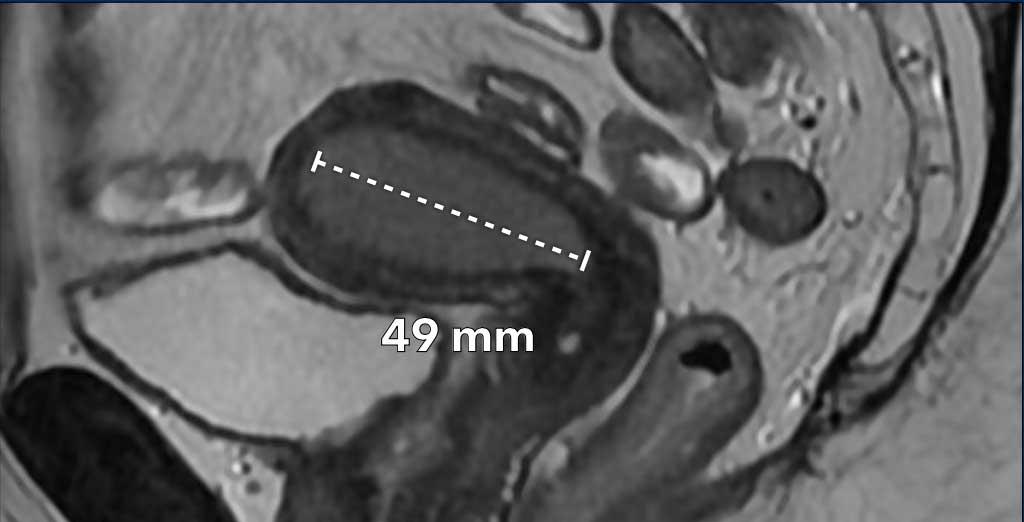

Hình ảnh

Ví dụ về một khối u nội mạc tử cung dạng tạo khối, thường dễ đo nhất. Điều quan trọng là phải đo đường kính dài nhất của khối u.

Trong trường hợp này, đường kính dài nhất của khối u được quan sát rõ nhất trên mặt phẳng đứng dọc (sagittal).

Trong các trường hợp dày lan tỏa hơn dọc theo lớp nội mạc tử cung, việc đo kích thước khối u có thể khó khăn hơn.

Hãy kiểm tra khối u trên nhiều mặt phẳng và tìm kích thước dài nhất có thể.

Trong trường hợp này, đường kính dài nhất của khối u được quan sát rõ nhất trên mặt phẳng ngang (axial) (hình).